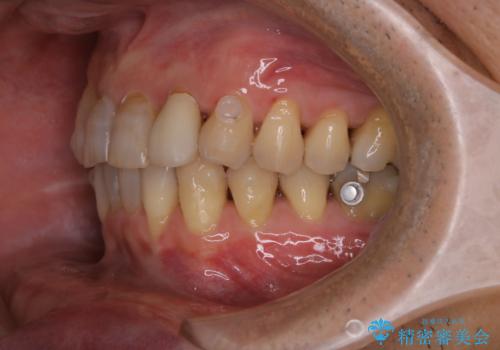

数年ぶりに歯のクリーニング(PMTC)